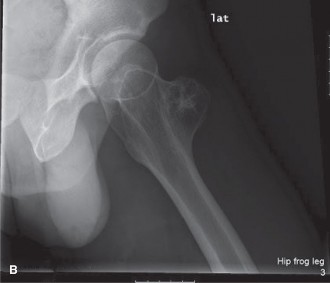

Radiographic Evaluation

Initial imaging included standard anteroposterior and lateral plain radiographs of the left femur and knee. The radiographs revealed a large, lytic lesion centered within the metadiaphyseal region of the distal femur. The lesion demonstrated an aggressive radiographic appearance characterized by ill-defined margins and a wide zone of transition. Significant endosteal scalloping was present, accompanied by frank cortical destruction, particularly localized to the lateral cortex.

Within the radiolucent matrix of the lesion, areas of faint, irregular calcification were clearly identified. These calcifications exhibited the classic "rings and arcs" and "flocculent" morphology, which is highly pathognomonic for a chondroid matrix. A patchy and discontinuous periosteal reaction was observed, indicative of a biological process that is expanding rapidly enough to outpace the periosteum's ability to lay down mature reactive bone. While severe cortical thinning and erosion were evident, no complete pathological fracture was identified.